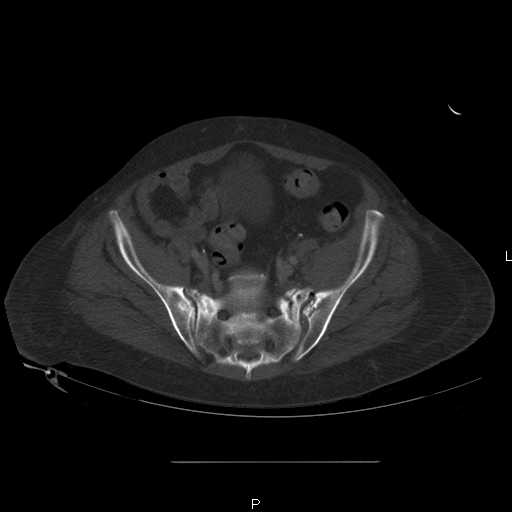

Here are a recent patient’s example slides...

54 yo Female Fell c/o Pain

3 Months After Fall

Continued Pain & Immobility

(+) Instability to Compressive Manual Exam

Pelvic CT Scan - 3 Months After Fall

Sacral Injuries

Ramus Fractures